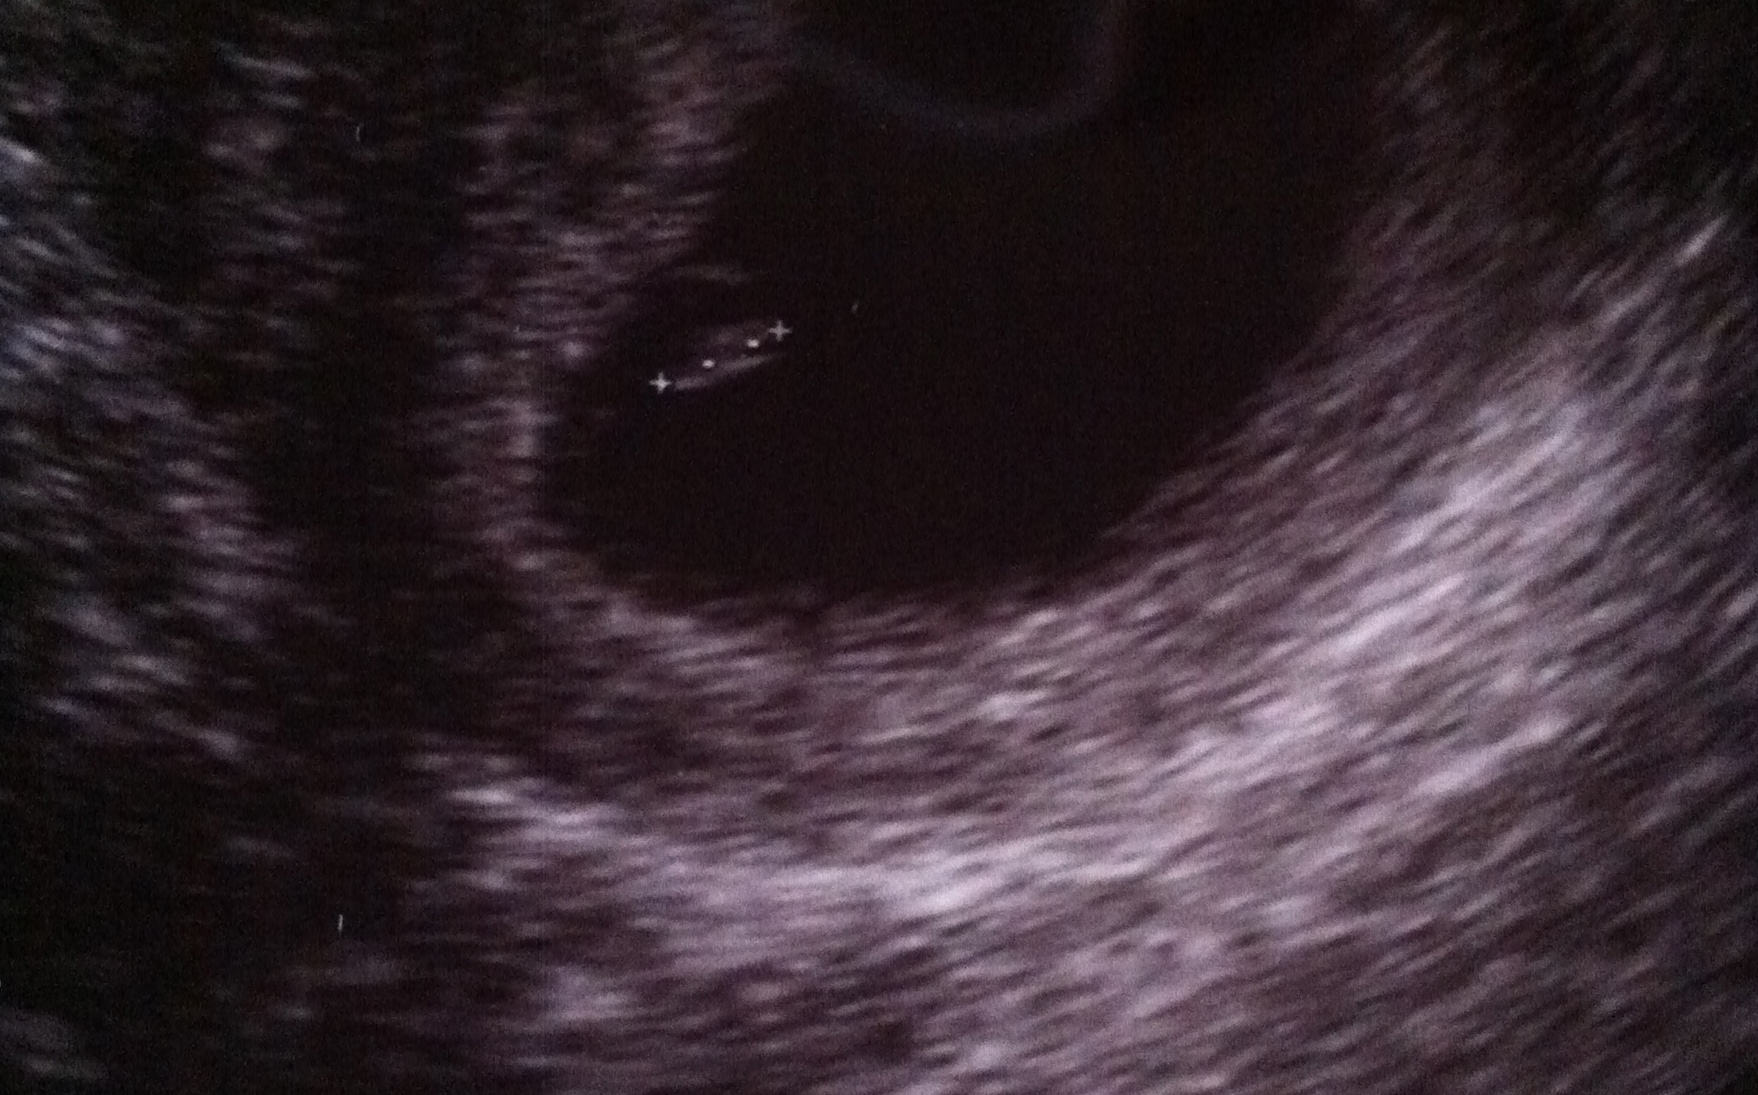

Then, it was time for our 12 week sonogram. On October 3rd, Dan, my mother, and I all drove to the appointment together. Finally, we would see our little one. That day, the walls came crashing down and my life changed forever. Seeing no baby on the screen put me in shock. When the tech left the room to get the doctor, my Mom chose to break the sad news to us. She is a retired ultrasound technician and has been in the field for years. She knew right away. She stood up, and told me that the baby stopped developing. I had a blighted ovum, or a missed abortion as its also called. I was still in shock. Dan just stood there and looked at me. My Mom hugged us both and was very upset. The only words that came out of my mouth were what, how, and why…

Since that ultrasound, I had started to bleed lightly. It seemed at the time that my body has started the process to miscarry naturally. And even though I said I wanted to get the D&C procedure to end it all quickly, I really just wanted my body to do its thing. That next Tuesday, the 7th, I saw another doctor and had another ultrasound. This, again, confirmed the baby had not developed. All there was inside me was the empty sac. It was no surprise this time so I just went along with the appointment to get it over with. The doctor said I had the option to get the procedure but it did seem like my body was doing its thing so giving it time was something to consider. I chose time. Now, if only someone had prepared me for what was coming.